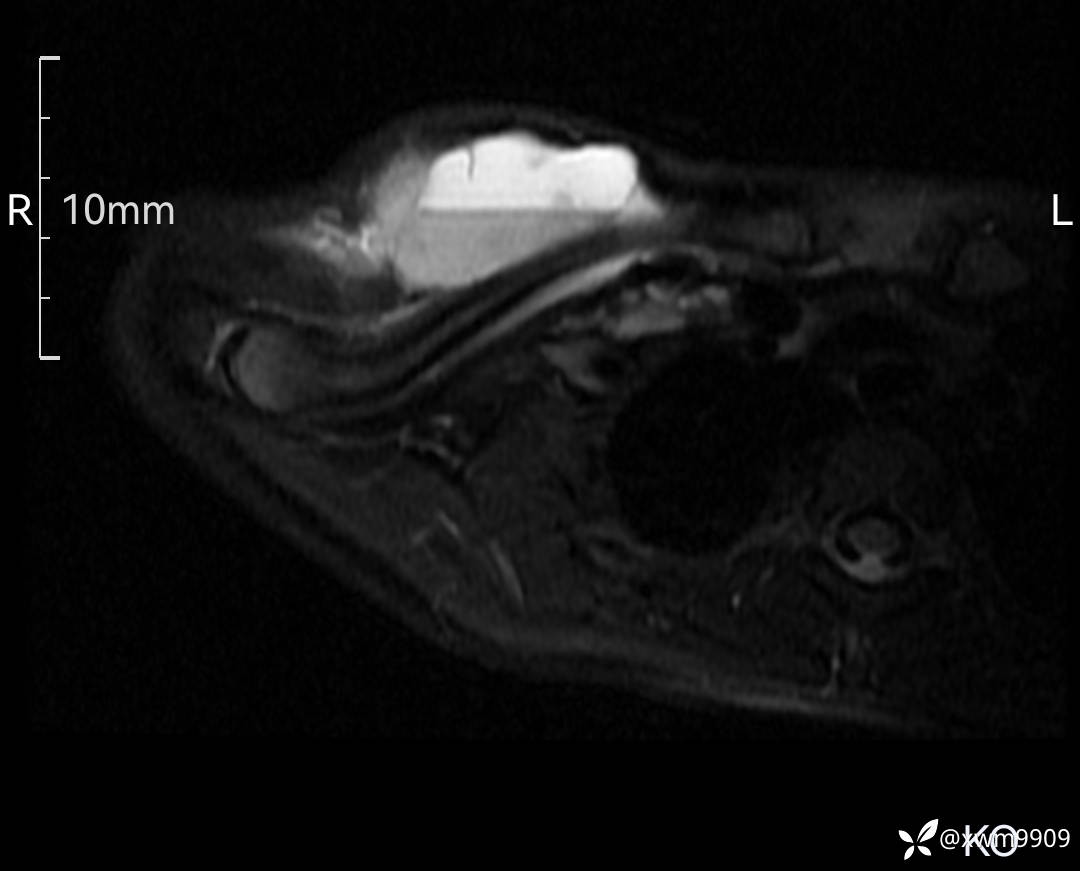

3、查体,右锁下方可及一约5x6Cm肿物,软丶边清丶未见明显发红,肤温不高,压痛明显,不可推动,稍有波动感。其他无特殊。

CT:

2、CT、MR肿块内可见液-液平面,常见有哪些疾病。

3、如何定性、定病?